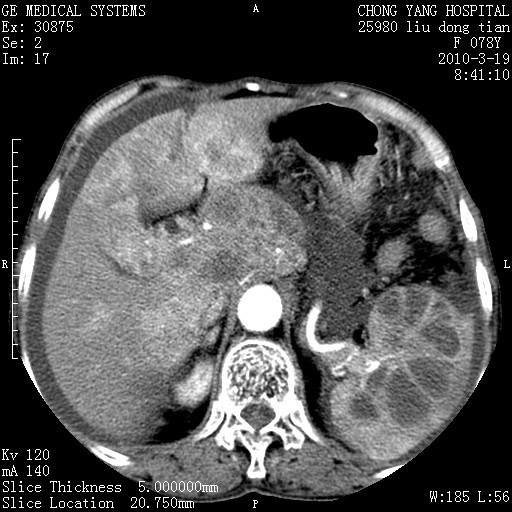

标题: CT25199:F 78Y 腹胀半年 消瘦乏力 [打印本页]

胆囊壁增厚并明显强化,胆囊癌伴多发转移瘤可能性大,淋巴瘤不除外,右肾囊肿,胸腹水.

考虑nhl,肝、脾、腹膜腔及腹膜后多发淋巴结受侵,腹水,右肾囊肿,慢性胆囊炎,右侧少量胸腔积液。

胰头有肿块形成,胰头ca伴肝脾、腹膜腹膜后转移

胆囊有软组织影有强化,支持胆囊癌,肝脾、腹膜后淋巴结转移。

nhl的淋巴结多围绕主动脉,而且主动脉会移位,所以不考虑nhl。

分开来讲:肝左叶、尾叶病灶有不均强化像肝癌;

脾脏病灶无强化,像多发囊肿或淋巴管瘤,不除外淋巴瘤(低强化);

胆囊增生性病变:胆囊癌,腺肌增生症,慢性胆囊炎;

肝门、胰腺头、腹膜后多个团块: 淋巴瘤,转移;

腔静脉肝内段细小有无布加可能?

一元论最好了 淋巴瘤所致改变; 胆囊癌转移不像,胆囊周围肝组织清晰,肝癌淋巴结转移?三元论都不止。

胰头ca伴肝脾、腹膜腹膜后转移!

最后报的胰头癌多发转移,脾脏单独考虑囊肿或淋巴管瘤。